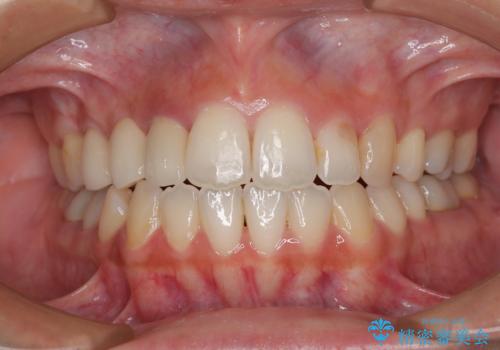

前歯のクロスバイトをインビザラインで矯正治療

- 前歯のデコボコとクロスバイトを気にして来院された患者様です。

前歯を早く整えたいとの希望があったので、ワイヤー矯正にて短期間でクロスバイトを解消し、その後インビザラインにて整えることとしました。

インビザラインによる前歯のクロスバイト改善におけるリスクとして、前歯歯髄充血・歯髄壊死が挙げられます。

ワイヤー矯正を併用する目的として、短期間でデコボコやクロスバイトを改善する他に、歯髄充血リスクを低減させるというものがあります。